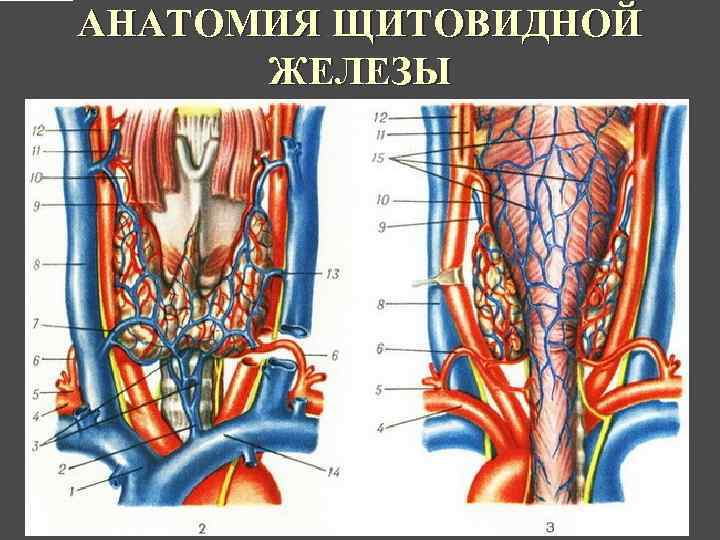

АНАТОМИЯ ЩИТОВИДНОЙ ЖЕЛЕЗЫ

АНАТОМИЯ ЩИТОВИДНОЙ ЖЕЛЕЗЫ

АНАТОМИЯ ЩИТОВИДНОЙ ЖЕЛЕЗЫ